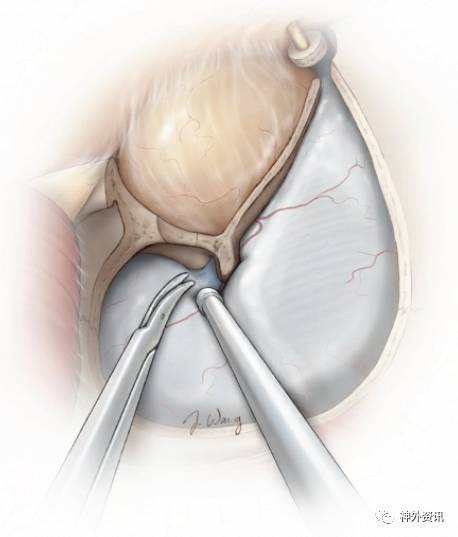

图27:用小而薄的骨凿,从之前游离眶上神经的眶缘切口,由内向外,沿着眶顶完成最后一步眶骨切开术。眶顶骨质可极为菲薄,因此避免使用蛮力捶打骨凿。

图28:另一种完成眶骨切开术的方法是,用相同的骨凿对着关键孔凿开眶顶。用两块脑棉分别保护前下方的眶骨膜和后上方的额叶硬膜,以免受到骨凿损伤。